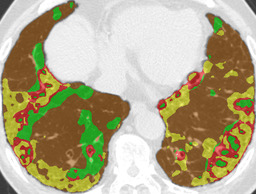

Recall, precision, and dice coefficient (a.k.a F-measure) were used for the evaluation. For the sake of the evaluation, continuous softmax outputs were converted into discrete class labels by selecting the classes that gave the maximum probability. Table 2 shows the evaluated metrics for each method. By paired t-tests, statistically significant differences were confirmed between the proposed method (λ=0.1𝜆0.1\lambda=0.1) and other methods in dice coefficients. As shown in Table 2, utilizing weakly annotated pixels increased precision and λ=0.1𝜆0.1\lambda=0.1 was the optimal value that balances recall and precision in this experiment. Evaluated dice coefficients for the proposed method (λ=0.1𝜆0.1\lambda=0.1) are shown in Figure 2. As shown in Figure 2, even though the proposed method improved the segmentation accuracy, segmentation accuracy varies between slices. Figure 3 shows the confusion matrix of the pixel-wise classification result. In Figure 3, Lweaksubscript𝐿𝑤𝑒𝑎𝑘L_{weak} pixels misclassified as corresponding Lstrongsubscript𝐿𝑠𝑡𝑟𝑜𝑛𝑔L_{strong} (e.g. pixels of lCON¯subscript𝑙¯𝐶𝑂𝑁l_{\overline{CON}} classified as lCONsubscript𝑙𝐶𝑂𝑁l_{CON}) are represented as “Others”. As shown in Figure 3, DLD class combinations with similar texture patterns such as HCM and EMP were misclassified into each other. Figure 4 shows the average result for each DLD class and tested method.

Ground truth Supervised only Proposed (λ=0.1𝜆0.1\lambda=0.1) Proposed (λ=1𝜆1\lambda=1)

CON \blacksquare

Refer to caption Refer to caption Refer to caption Refer to caption

0.839 0.868 0.824

GGO \blacksquare

0.693 0.676 0.876

HCM \blacksquare

0.581 0.770 0.435

EMP \blacksquare

0.793 0.847 0.815

NOR \blacksquare

0.978 0.968 0.974

Figure 4: Average results and dice coefficients for each DLD pattern. Automated segmentation results are superimposed with colors. For each DLD pattern, the slice that gave the median dice coefficient for the proposed method with λ=0.1𝜆0.1\lambda=0.1 was chosen to represent the average result. Note that although CNN performed multi-class segmentation, only one DLD pattern per slice was taken into account for the evaluation.